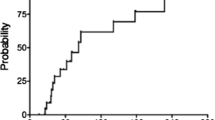

At the time of this writing, 34 were alive and free of the primary disease, recurrence, or the development of secondary neoplasms other than cavernous angioma; 5 died of recurrence, 1 died of secondary leukemia, and 1 was alive with recurrence of the primary disease. Following irradiation treatment, 11 patients developed 19 cystic malacia during a median course of 30.8 months with a range from 14.9 to 59.3 months (Fig. 1). The site of predilection for cystic malacia was white matter around trigone of lateral ventricles with the incidence of 47.4% (9 of 19 lesions, 7 in 11 patients). Even two of our patients with posterior fossa tumors developed cystic malacia around trigone of lateral ventricle. Other sites for development of cystic malacia were as follows: five in frontal, two in parietal, two in temporal, and one in cerebellum. Children treated at an age younger than 4.5 years developed cystic malacia significantly earlier than those who were at least 4.5 years old (Fig. 2; median 32.2 months vs not reached, P = 0.0169, log-rank test).

Patients with supratentorial tumors (n = 20) developed cystic malacia more frequently than the patients with infratentorial tumors (n = 21) (Fig. 3a; P = 0.0178, log-rank test). Similarly, patients with supratentorial tumors developed Zabramski type 1 and 2 cavernous angiomas significantly earlier than the patients with infratentorial tumors (Fig. 3b; P = 0.0157, log-rank test). There was no difference in the development of Zabramski type 3 and type 4 cavernous angiomas between supratentorial and infratentorial tumors (P = 0.8754, log-rank test). In our study, patients with supratentorial tumors developed white matter changes significantly earlier than did the patients with infratentorial tumors (Fig. 3c; P = 0.0007, log-rank test). Nineteen of 41 patients developed grade 1 leukoencephalopathy, while no patients developed grades 2–4 leukoencephalopathy (CTCAE version 3.0).

a Probability of developing cystic malacia in 41 pediatric patients who were followed for more than 12 months after high-dose craniospinal irradiation for brain tumors. Comparison was done between patients with supratentorial and infratentorial tumors. b Probability of developing Zabramski type I and II cavernous angiomas in 41 pediatric patients who were followed for more than 12 months after high-dose craniospinal irradiation for brain tumors. Comparison was done between patients with supratentorial and infratentorial tumors. c Probability of developing white matter change in 41 pediatric patients who were followed for more than 12 months after high-dose craniospinal irradiation for brain tumors. Comparison was done between patients with supratentorial and infratentorial tumors